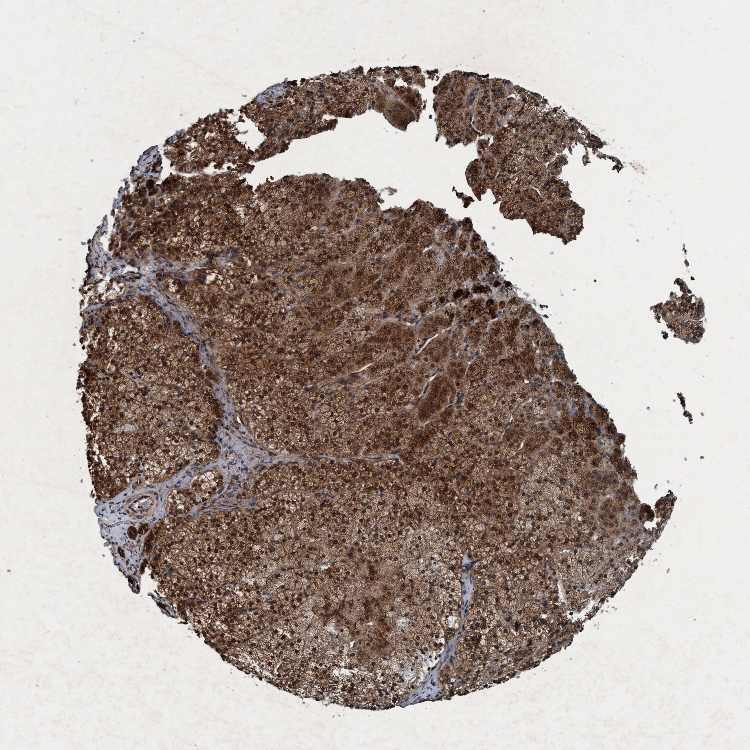

ADRENAL GLAND - Antibody stainingi

Antibody staining in the annotated cell types in the current human tissue is reported as not detected, low, medium, or high, based on conventional immunohistochemistry profiling in selected tissues. This score is based on the combination of the staining intensity and fraction of stained cells.

Each image is clickable and will lead to virtual microscopy that enables deeper exploration of all samples and also displays staining intensity scores, fraction scores and subcellular localization as well as patient and tissue information for each sample.

Antibody HPA064427Antibody HPA075510Antibody CAB021903

Glandular cells MediumMediumHigh